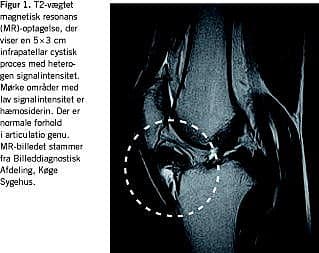

LPVS i knæet medfører progredierende, kroniske, unilaterale smerter og inflammatoriske symptomer med eksacerbationer. Aflåsning og bevægeindskrænkning forekommer. Differentialdiagnoser er bursitis, menisk- og brusklæsion, reumatoid artritis, lipom, synovialt sarkom og hæmangiom [1-3]. Makroskopisk er LPVS en gulligbrun nodulær struktur. Diagnosen stilles histologisk ved forekomst af skumceller, hæmosiderofager, histiocytter, kæmpeceller og synovialcelleproliferation [3]. Billeddiagnostisk anbefales magnetisk resonans (MR)-optagelser til påvisning af LPVS. På T1- og T2-vægtede MR-optagelser ses LPVS som væv med heterogen signalintensitet typisk afgrænset af en perifer mørk rand med nedsat signalintensitet, der skyldes aflejring af hæmosiderin. Røntgenoptagelser kan vise periartikulære trykerosioner og cystedannelse [2, 4].

I ambulatoriet fandt man en puklet, 5 × 3 cm stor, øm tumor lateralt for ligamentum patellae. Der var normal ekstension over knæleddet. Fleksion over 90 grader udløste forreste knæsmerter. Knæet var stabilt uden patellaanslag. En MR-skanning viste normale forhold i knæleddet og profund for ligamentum patellae en velafgrænset, infrapatellar proces, der blev opfattet som et synovialt ganglion (Figur 1 ). Et røntgenbillede viste normale forhold.